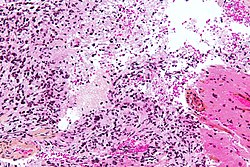

CNS lymphoma

General - primary CNS

- Classically periventicular distribution.

- Usually large B cell; can be considered a type of diffuse large B cell lymphoma (DLBCL).

Microscopic

Features:

- Large cell lymphoma.

- Size = 2x diameter normal lymphocyte.

- Nucleolus - common.

- Perivascular clustering.

Images